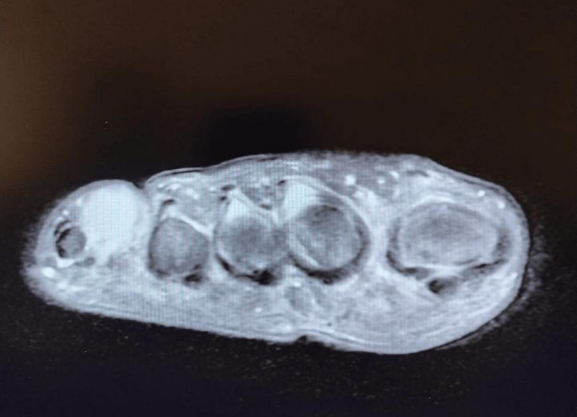

MRI: Revealed an oval-shaped mass on the medial and dorsal aspect of the fifth toe's proximal phalanx, measuring approximately 2 cm. It exhibited intermediate low signal intensity on T1-weighted images and mildly higher heterogeneous intermediate signal intensity on T2-weighted images, closely associated with the flexor tendon (Figures 1, 2 & 3)

FIGURE 2: MRI finding of the lesion (Aaxial view)